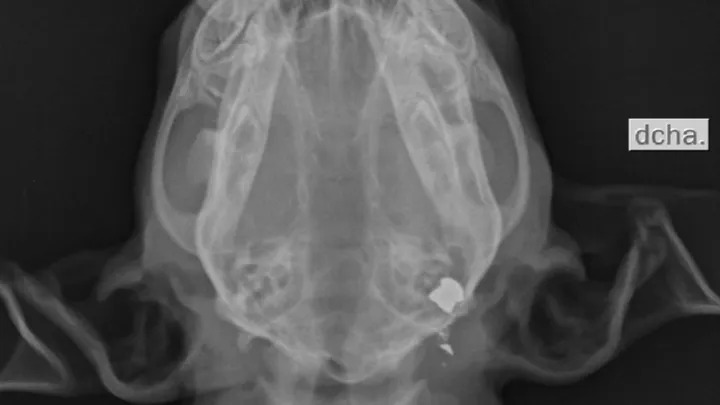

Ella estaba fuera el viernes por la mañana en mi patio trasero jugando como de costumbre, ella y su hermano se arrastró por debajo de la valla y se fue a nuestro patio de vecinos y ahí es donde la encontré . Al principio pensamos que la había matado un halcón, pero cuando le hicieron las radiografías de su cuerpecito nos dieron la horrible noticia de que le habían disparado con una escopeta de perdigones.” dio a conocer Zoraida Padilla, quien le dio hogar temporal.

Chloe ya estaba a punto de ser adoptada cuando este horrible suceso tuvo lugar y le arrebataron esa oportunidad. Si bien Chloe ya se encuentra en su hogar temporal, el perdigón sigue en la parte de atrás del cráneo de la cachorrita, actualmente no se le puede hacer una cirugía para retirarlo debido a su débil estado de salud; se le están aplicando 6 medicamentos diferentes que controlar la inflamación en su cerebro, así como para evitar una hemorragia cerebral y una infección.